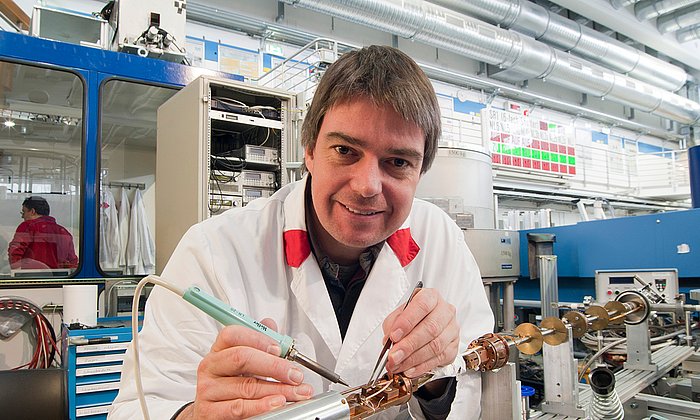

Dem geht nun Josef Lichtinger in seiner Doktorarbeit am Lehrstuhl für Physik der Hadronen und Kerne (E12) der TUM nach. Von der Rechtsmedizin der Ludwig-Maximilians-Universität München (LMU) erhielt er Gewebeproben von Patienten, die mit Lithium behandelt wurden, unbehandelten Patienten und gesunden Vergleichspersonen. Diese setzte der Physiker am Messplatz der Prompten Gamma Aktivierungsanalyse am FRM II einem fokussierten kalten Neutronenstrahl höchster Intensität aus.

Lithium reagiert sehr spezifisch mit Neutronen und zerfällt in ein Helium- sowie ein Tritiumatom. Mit einem speziellen Detektor, den Josef Lichtinger entwickelt hat, können deshalb so geringe Mengen wie 0,45 Nanogramm Lithium pro Gramm Gewebe gemessen werden. „So genau wie mit Neutronen kann man das mit keiner anderen Methode nachweisen“, sagt Jutta Schöpfer, Rechtsmedizinerin an der LMU, die mehrere Forschungsprojekte zur Lithiumverteilung im menschlichen Körper betreut.